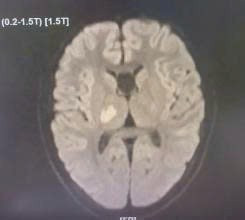

Hình ảnh chụp MRI não bộ của trẻ khi có dấu hiệu đột quỵ - Ảnh BVCC